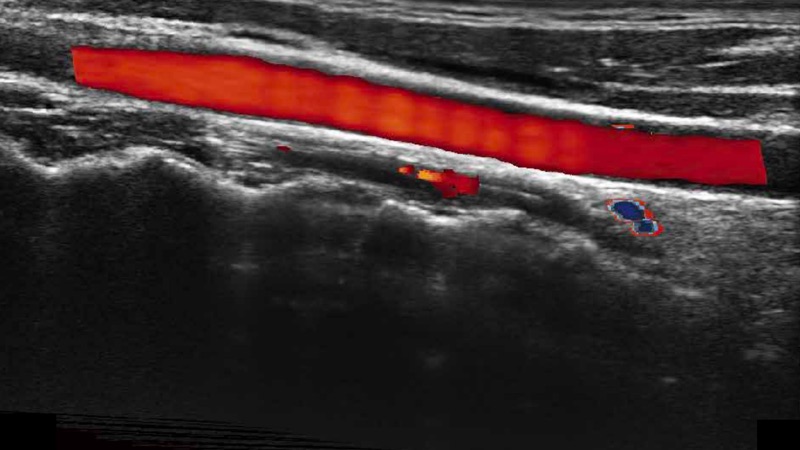

通過色彩血流和實時寬景相結(jié)合,可觀察到完整的靜脈或動脈的血流,方便醫(yī)生檢查。實時掃查過程中,如有任何操作失誤也可以很容易地進行回掃擦除,而不會中斷掃查。